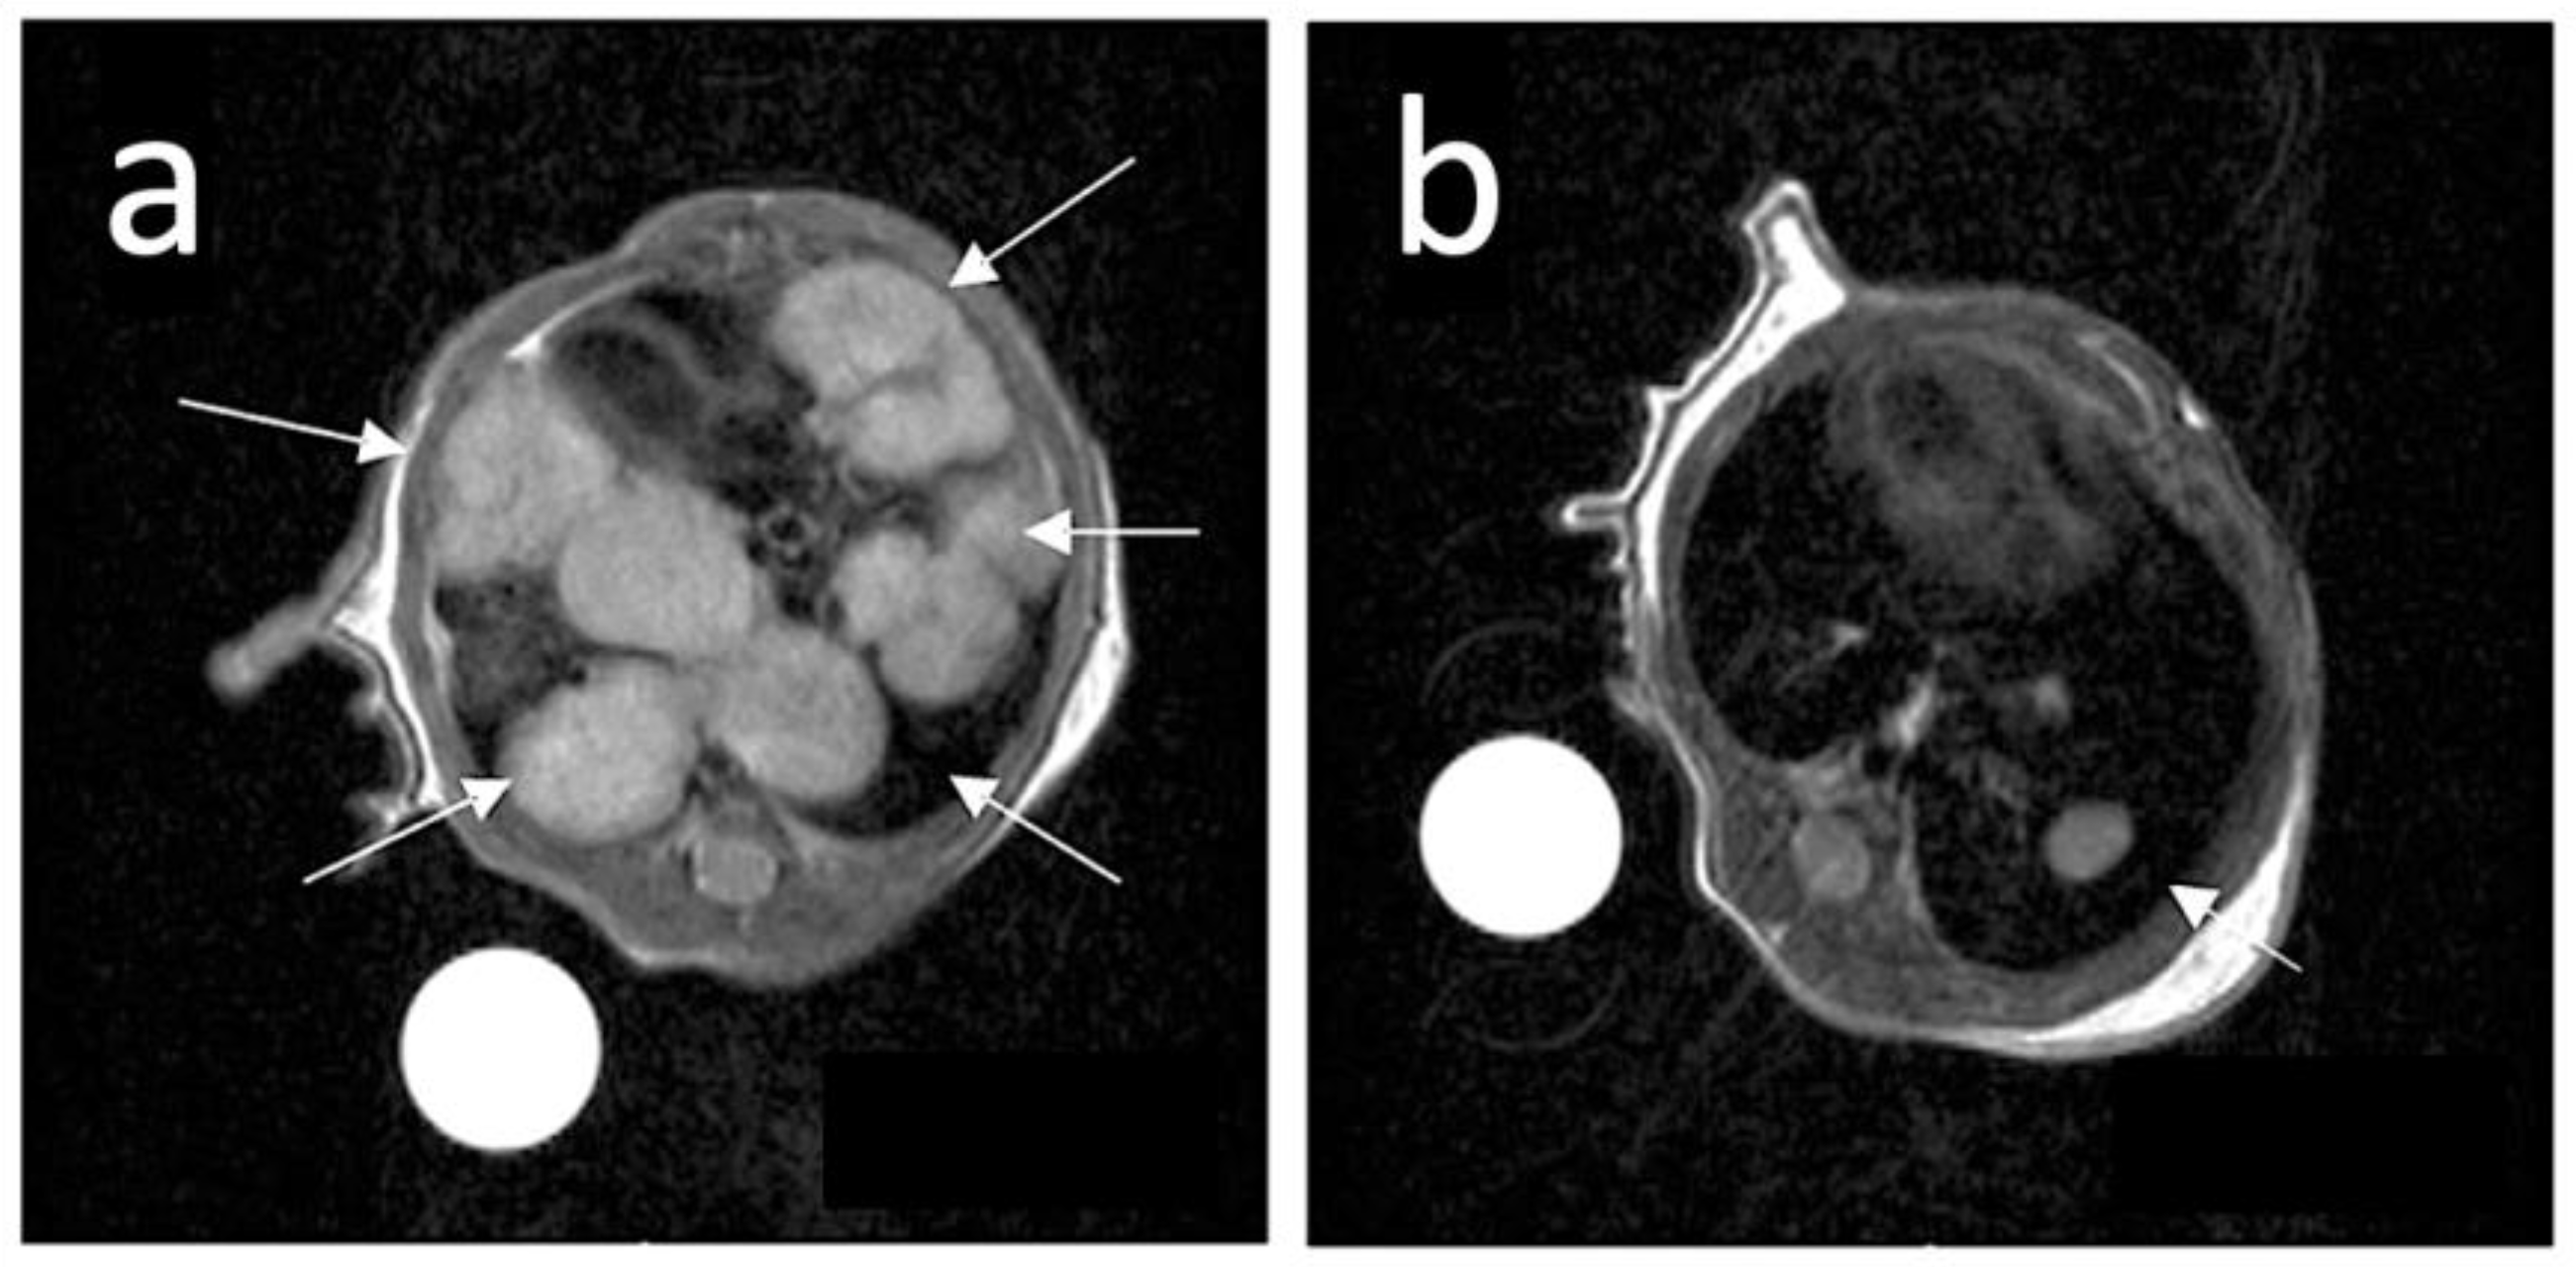

3.5. Magnetic Resonance Imaging (MRI)